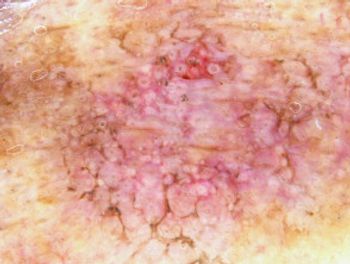

A recent retrospective cohort study described drug survival and treatment patterns among patients with newly-diagnosed generalized pustular psoriasis.